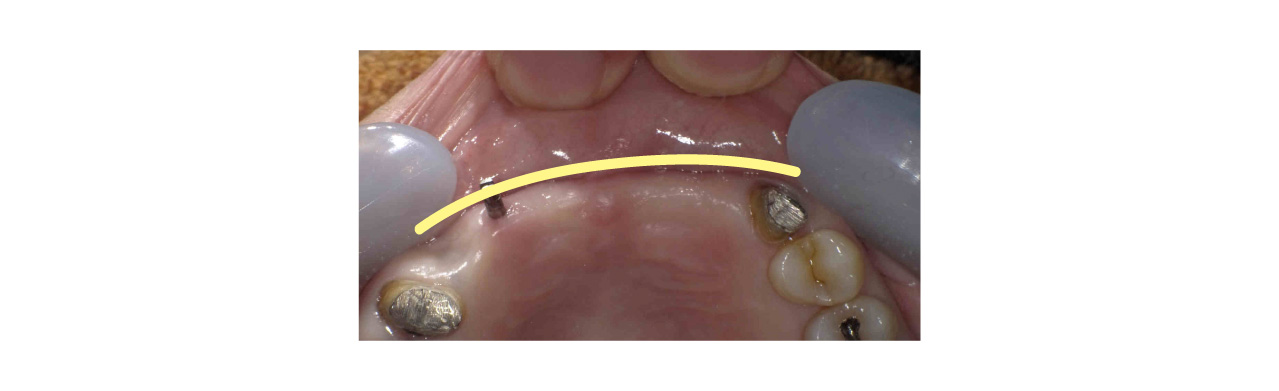

ここで、インプラント周囲には天然歯の1.5倍の厚みの歯肉が必要になります。インプラント周りの歯肉の厚みが2mm以下だと1.45mm骨が吸収し、2.5mmだと骨が吸収しないと言われています。しかし、歯を失ってからは骨が吸収するだけではなく歯肉も吸収する為インプラント周囲には薄い歯肉しか存在しません。特に頬側の歯肉が吸収され薄くなります。

そこでインプラントの頬側に分厚い歯肉を作る必要があります。

前回お話した角化歯肉を作る処置でも口蓋から歯茎を切り取って移植してましたが、今回は表に貼るのではなく、歯茎の中に移植します。カンガルーの袋の中に入れ込むイメージです